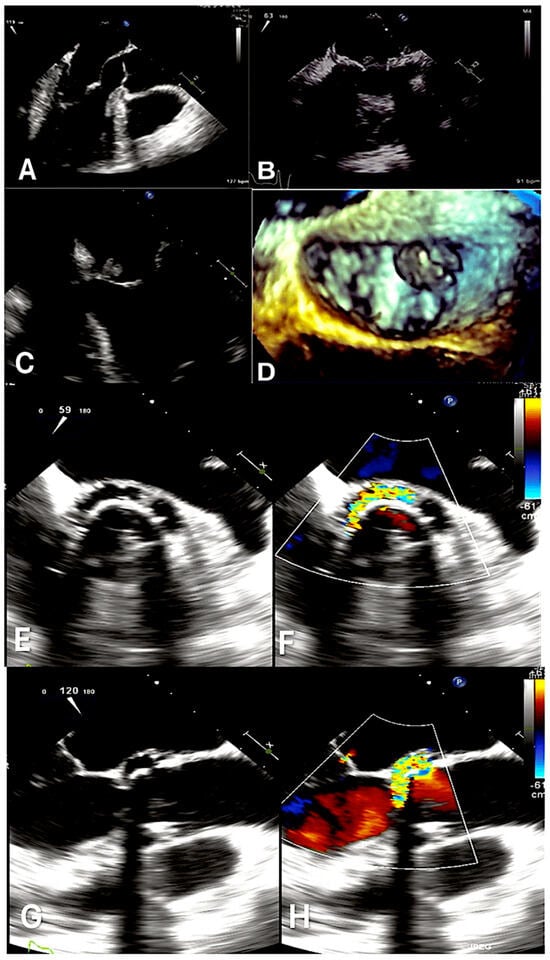

- In the case where transesophageal echocardiography (TEE) is more sensitive than transthoracic echocardiography (TTE) for identifying valvular vegetations and periannular complications of NVE, TEE should be employed as the initial diagnostic tool. This is in contrast to TTE, which may yield false negative or nondiagnostic results.

- Afonso, L.; Kottam, A.; Reddy, V.; Penumetcha, A. Echocardiography in infective endocarditis: State of the art. Curr. Cardiol. Rep. 2017, 19, 127. [Google Scholar] [CrossRef]

- Avtaar Singh, S.S.; Costantino, M.F.; D’Addeo, G.; Cardinale, D.; Fiorilli, R.; Nappi, F. A narrative review of diagnosis of infective endocarditis-imaging methods and comparison. Ann. Transl. Med. 2020, 8, 1621. [Google Scholar] [CrossRef]

- Habib, G.; Badano, L.; Tribouilloy, C.; Vilacosta, I.; Zamorano, J.L.; Galderisi, M.; Voigt, J.U.; Sicari, R.; Cosyns, B.; Fox, K.; et al. Recommendations for the practice of echocardiography in infective endocarditis. Eur. J. Echocardiogr. 2010, 11, 202–219. [Google Scholar] [CrossRef] [PubMed]

- Bai, A.D.; Steinberg, M.; Showler, A.; Burry, L.; Bhatia, R.S.; Tomlinson, G.A.; Bell, C.M.; Morris, A.M. Diagnostic accuracy of transthoracic echocardiography for infective endocarditis findings using transesophageal echocardiography as the reference standard: A meta-analysis. J. Am. Soc. Echocardiogr. 2017, 30, 639–646.e8. [Google Scholar] [CrossRef] [PubMed]